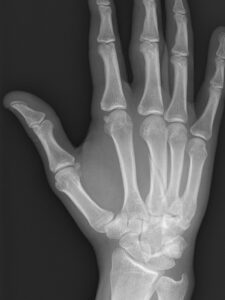

- XRAY – gold standard metacarpal fracture diagnosis

See below the two treatment approaches for a patient who has metacarpal fracture.

Fig 2: Action Rehab Hand Therapy Clinic Treatment

Your Action Rehab Hand Therapy Clinic hand therapist will fabricate a custom thermoplastic splint which will allow for healing and union of the fracture, followed by an array of ranging and stability exercises. The primary goals of treatment are to achieve acceptable alignment, stable reduction, strong bony union, and unrestricted motion.